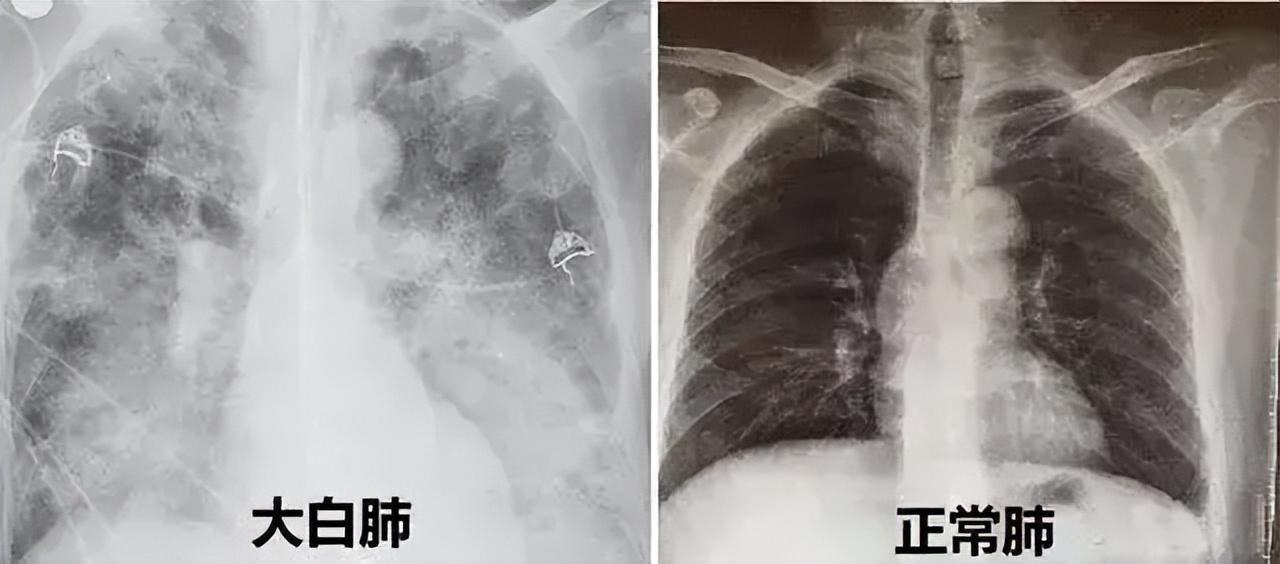

全称是急性呼吸窘迫综合征(ARDS),是患者在X光或者CT检查下,肺部显影呈一大片白色而得名,由肺部细菌感染或人体炎症反应所致。

健康的肺,在CT上显示应该是黑黑的,在CT片的透射下,很容易透过去,空气含量看起来很多。

而如果整个肺部看上去都是白的一片,那多半就是“白肺”。

(注意:不是出现炎症就都叫白肺,白肺属于比较严重的肺炎表现。一般白色面积达到70%-80%,在临床上口语化称为白肺。)